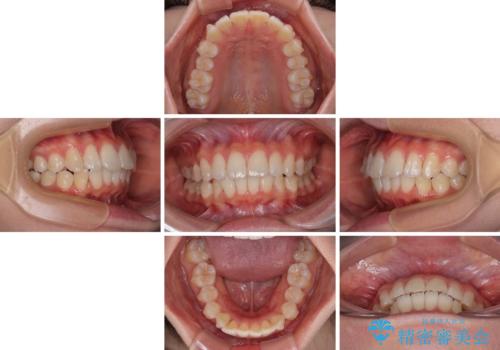

深い咬み合わせによる隙間 インビザライン矯正でコンプレックスを改善

インビザラインにより、上下の歯列を側方に拡大しつつ、前歯の隙間を閉じていくこととしました。

隙間の原因は強い咬合力や舌の突出癖、小帯の異常付着などがありますが、舌のトレーニングをしっかりと行いながら、装着時間を遵守して装着していただいたおかげで、スムーズに治療を終えることができました。